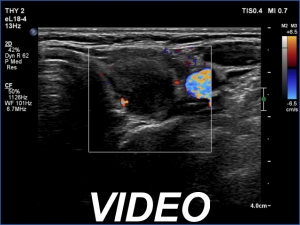

Third examination 6 months after the previous visit (third row of images):

Clinical data: The patient had no complaints.

Palpation: no abnormality.

Laboratory tests: TSH 2.97 mIU/L, aTPO 28 U/mL on daily 50 microgram levothyroxine.

Ultrasonography. The pattern remained unchanged except for the disappearance of the large, ill-defined lesion in the left lobe.

Suggestion: daily 50 microgram levothyroxine, TSH in a year.